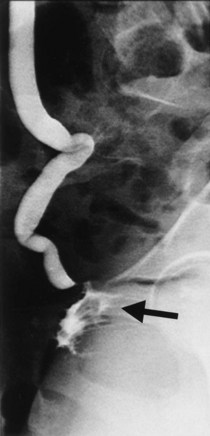

A cystogram and/or voiding cystourethrogram (VCUG) and an upper tract study should be performed in patients being evaluated for a VVF. The cystogram may objectively determine the presence and location of the fistula. Upon filling of the bladder, contrast often begins to opacify the vagina, almost immediately confirming the presence of a VVF. VVF are often best seen in the lateral projection (Fig. 77–7) in which the bladder and vagina are not superimposed. Often, the actual VVF tract may be visible in the lateral projection (Fig. 77–8). However, voiding images may be necessary in some patients with small fistulae, to demonstrate the VVF. The slight increase in intravesical pressure that accompanies micturition is usually adequate to demonstrate even very small fistulae. Importantly, a cystogram that fails to demonstrate a suspected VVF, but lacks voiding images or postvoid images, should be considered nondiagnostic. During voiding, care should be taken to exclude vaginal voiding or reflux of contrast from the introital region cephalad into the vagina, which would produce a falsely positive image. An involuntary bladder contraction can be provoked with rapid filling during cystography, and if the intravesical pressure rises sufficiently, this may also be sufficient to demonstrate a VVF when the filling images of the cystogram failed to demonstrate it. In some instances, a cystogram can also make an assessment of bladder capacity (important in the setting of prior radiotherapy), cystocele, bladder neck competence, and vesicoureteral reflux, any of which may have an impact on operative repair.

Figure 77–7 Cystogram demonstrating a vesicovaginal fistula (VVF). A, Lateral image demonstrates a posthysterectomy VVF. B, Anteroposterior view. The contrast agent is seen opacifying and outlining the vagina superimposed on the bladder.